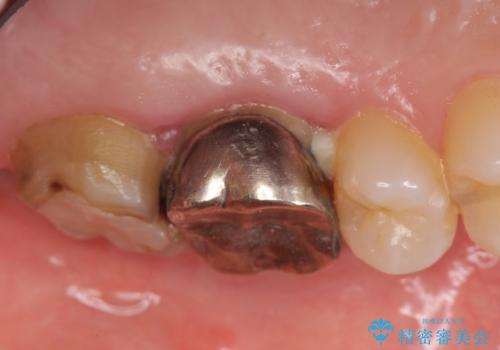

検査の結果左上6に打診痛、根尖部圧痛、根尖病変を認めたため、再根管治療を行ったところ症状が緩解したため、オールセラミッククラウンによる補綴を行いました。

左上7は治療を希望されなかったため、オールセラミッククラウンによる補綴のみを行いました。

- オールセラミッククラウン…¥100,000×2、仮歯…¥10,000×2、ファイバーコア…¥20,000費用は治療当時の料金となります